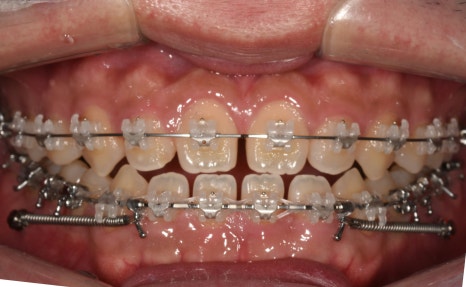

오늘 살펴볼 세라믹치과의

반대교합 치아교정전후 사례는

반대교합, 아래턱 돌출, 비발치 교정으로

진행한 증례입니다.

-부정교합 개선을 위한 '비발치 교정'

(예상 기간 24개월)

치료결과

실제 소요 기간 : 14개월

반대교합과 불규칙한 치아배열,

아래턱 돌출 등의 문제사항이

확연히 개선된 것을 알 수 있습니다.

예상 교정기간이 24개월이었으나

빠른 치아의 이동으로

10개월 단축된 14개월만에

빠르게 교정을 완료하였답니다.

교정과정

한눈에 보기

1 / 2

3 / 4